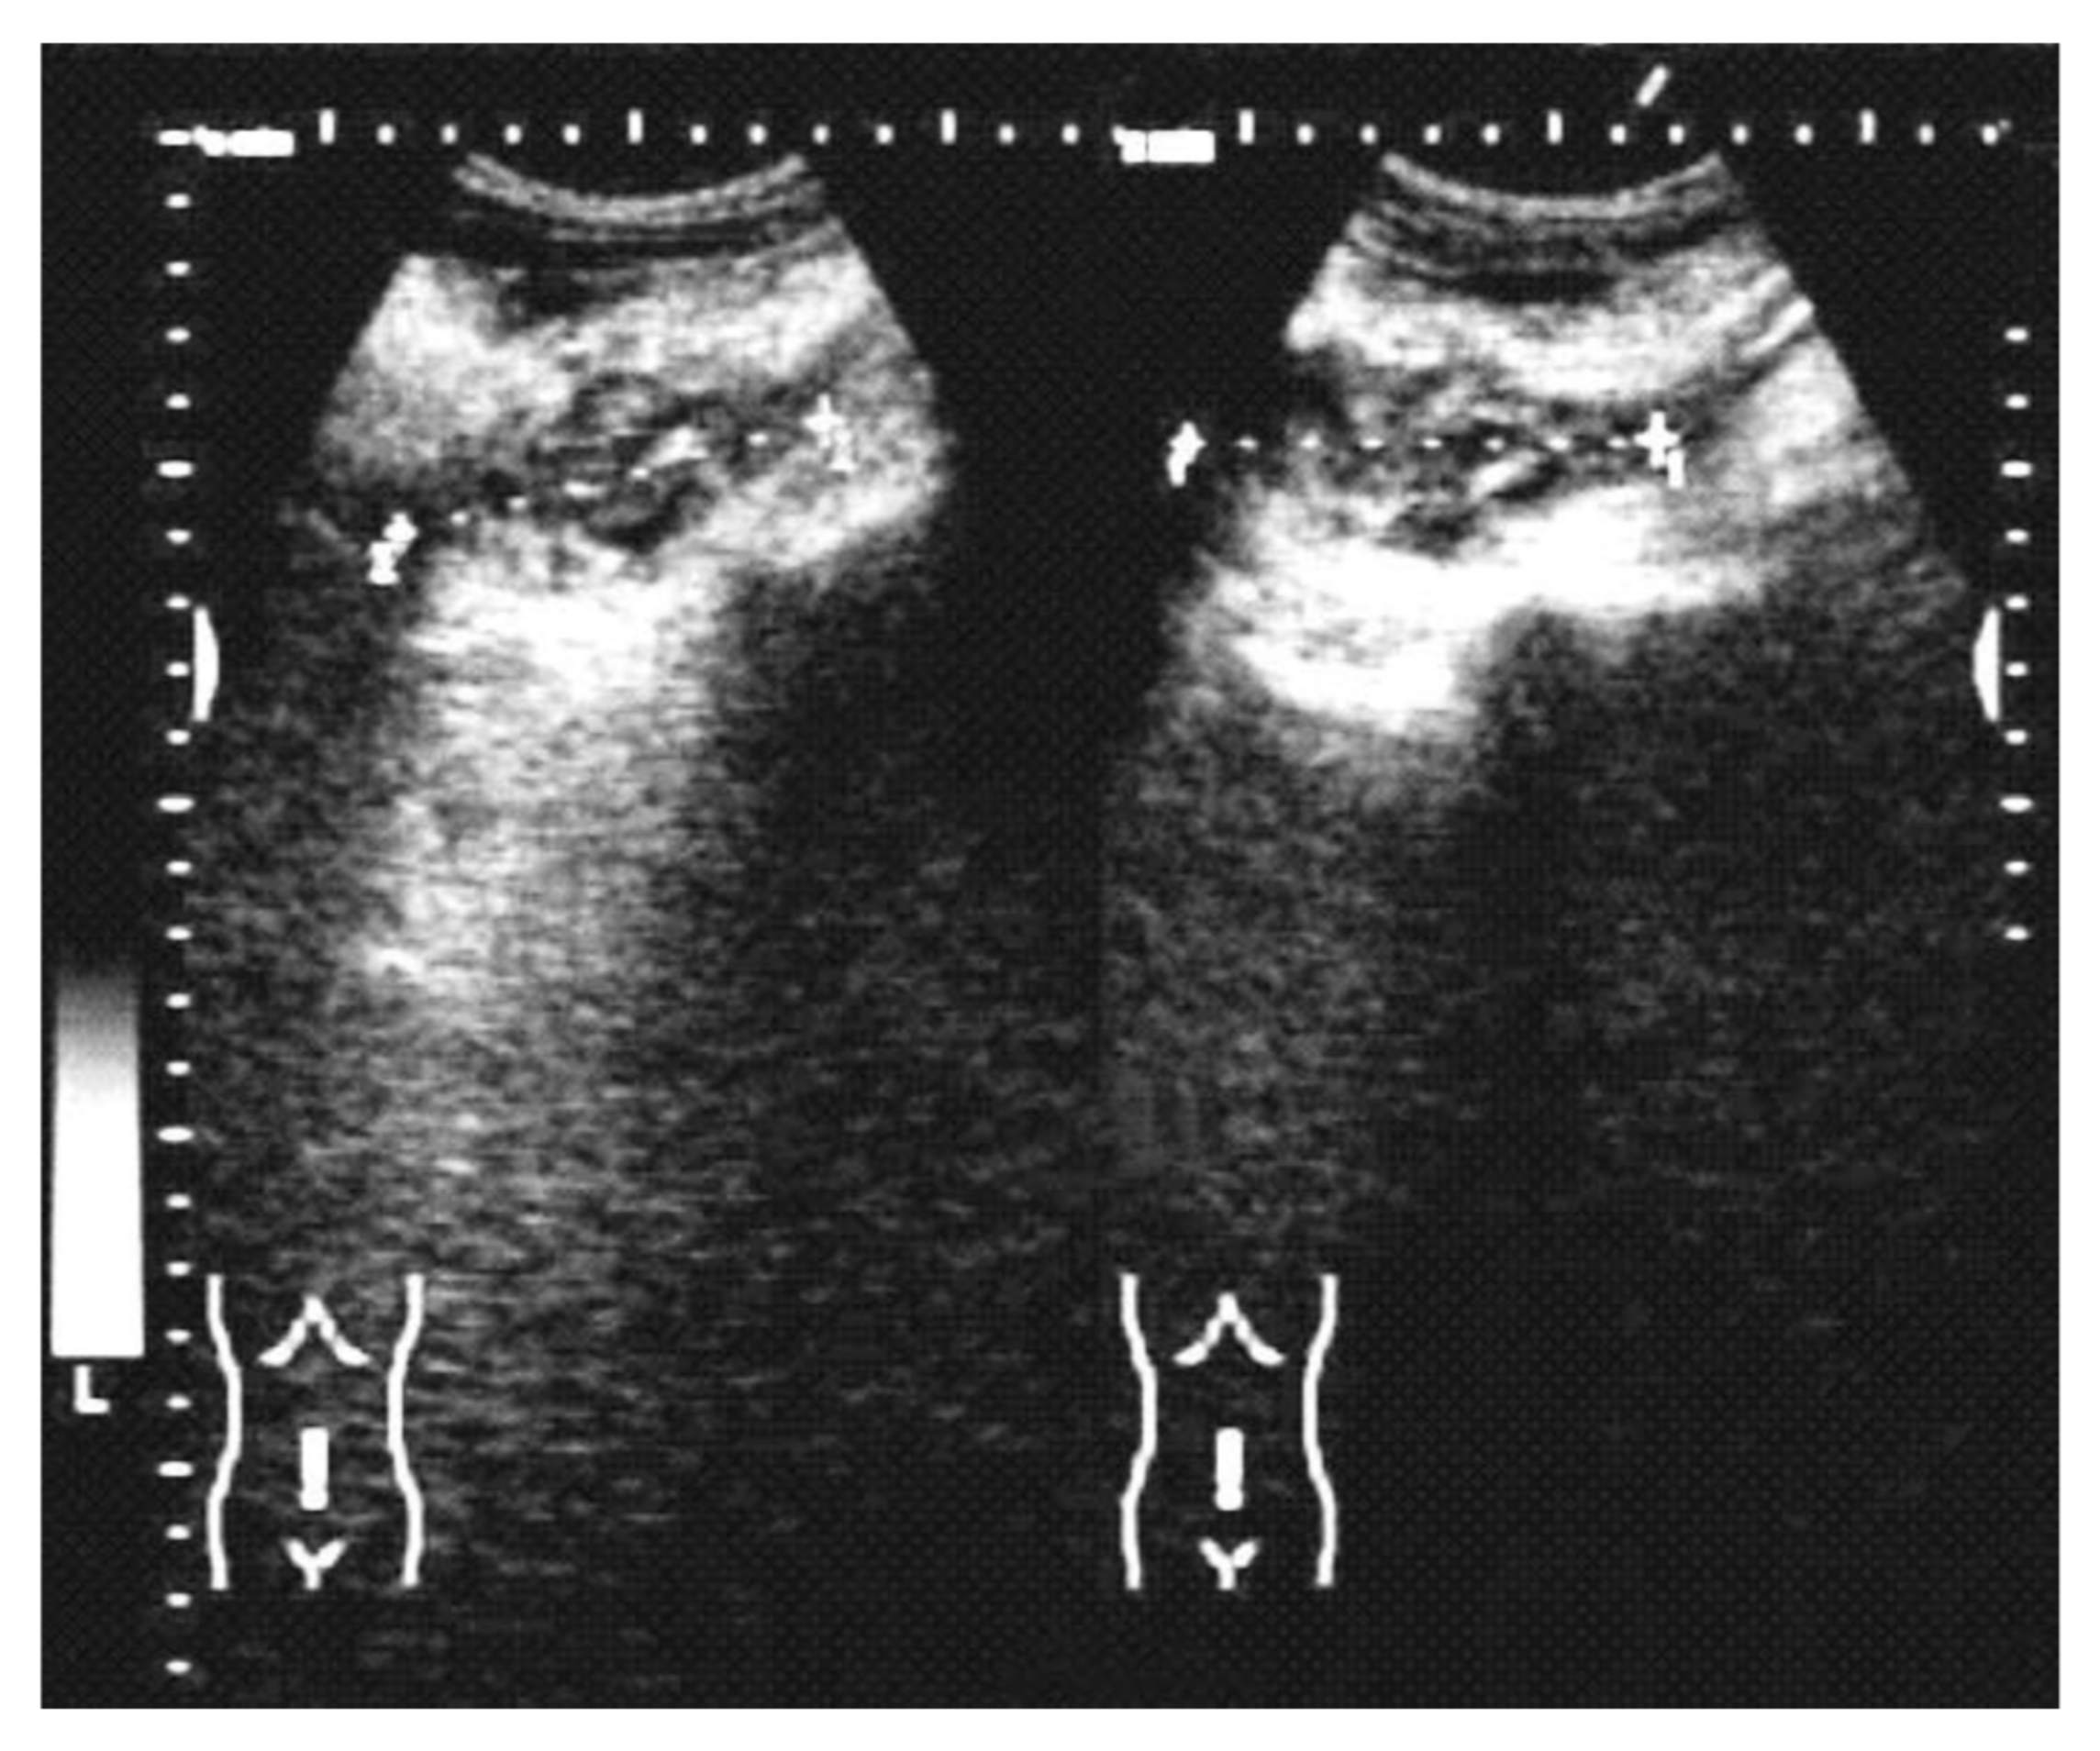

The disease was rarely suspected on imaging and was usually noncontributory to the positive diagnosis. The abdominal ultrasound (Figure 1) described collections and abscesses found in the abdomen and pelvis, and there was also inflammatory involvement or a solid, heterogeneous mass, surrounded by collections confirmed by CT findings of the abdomen and pelvis (Figure 2), which showed the infiltrative nature of the disease, a heterogeneous mass involving a distal ileum, cecum, and ascending or transverse colon, and an inflammatory mass involving the ovaries for a pelvic tumor. Lab work revealed an elevated white count and anemia, and tumor markers were normal or with slightly modified values in most cases. We did not use polymerase chain reaction (PCR) for diagnosis.

Figure 1.

Abdominal ultrasound discovered a heterogeneous abdominal tumor and peritumoral fluid.